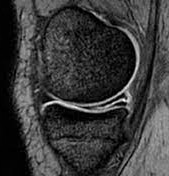

Desde que se introdujo la resonancia magnética nuclear como método de estudio radiológico en la década del 80, la manera de ver las estructuras de la rodilla y en especial los meniscos se ha ido modificando y ha permitido una precisión diagnóstica muy alta. Podemos ver los meniscos normales, su forma anatómica, sus variantes (como los meniscos discoides) y sus lesiones. Dentro de las lesiones meniscales, podemos detectar con una alta precisión el tipo de lesión de la que se trata: roturas radiales, longitudinales, horizontales, lesiones de la raíz meniscal, lesiones en rampa meniscal, lesiones con desplazamiento de fragmentos meniscales.

Para poder visualizar de manera correcta los meniscos y para poder detectar sus lesiones necesitamos estar atentos a varias cosas. Por un lado, la clínica y los antecedentes clínicos del paciente son de suma relevancia: conocer qué tipo de dolor tiene el paciente, cuál fue el mecanismo de la lesión, si se sospecha lesiones acompañantes, cuánto tiempo lleva el enfermo con la dolencia; por lo tanto contar con una buena revisión clínica y con una adecuada anamnesis es muy importante. Por otro lado, necesitamos que el estudio de RMN esté correctamente realizado, que se hayan hecho las secuencias correctas y los planos correctos para ver las distintas estructuras de la rodilla. Si mientras se realiza el estudio notamos que es necesario abarcar una región mayor o realizar una secuencia especial, es importante que lo hagamos, para que el estudio quede completo.